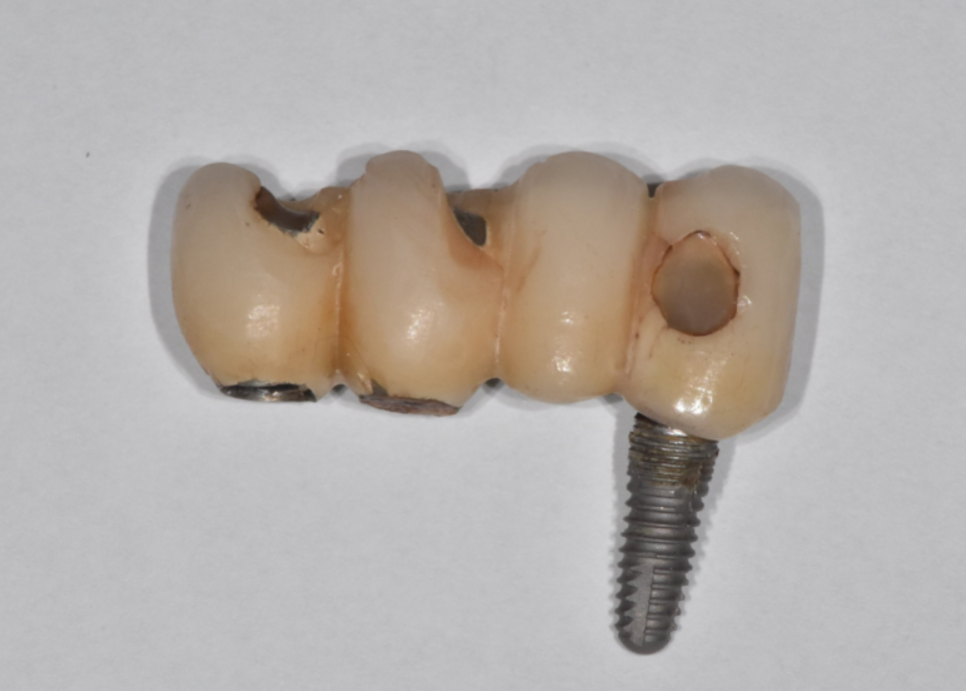

환자분이 빠진 것을 가지고 오셨는데

이런!!

임플란트가 통째로 빠졌습니다.

23.06.20

임플란트 브릿지 형태로 묶어놨었는데

그중 1개 임플란트만 빠졌습니다.

기둥처럼 보이는 것 아래에

임플란트가 있습니다.